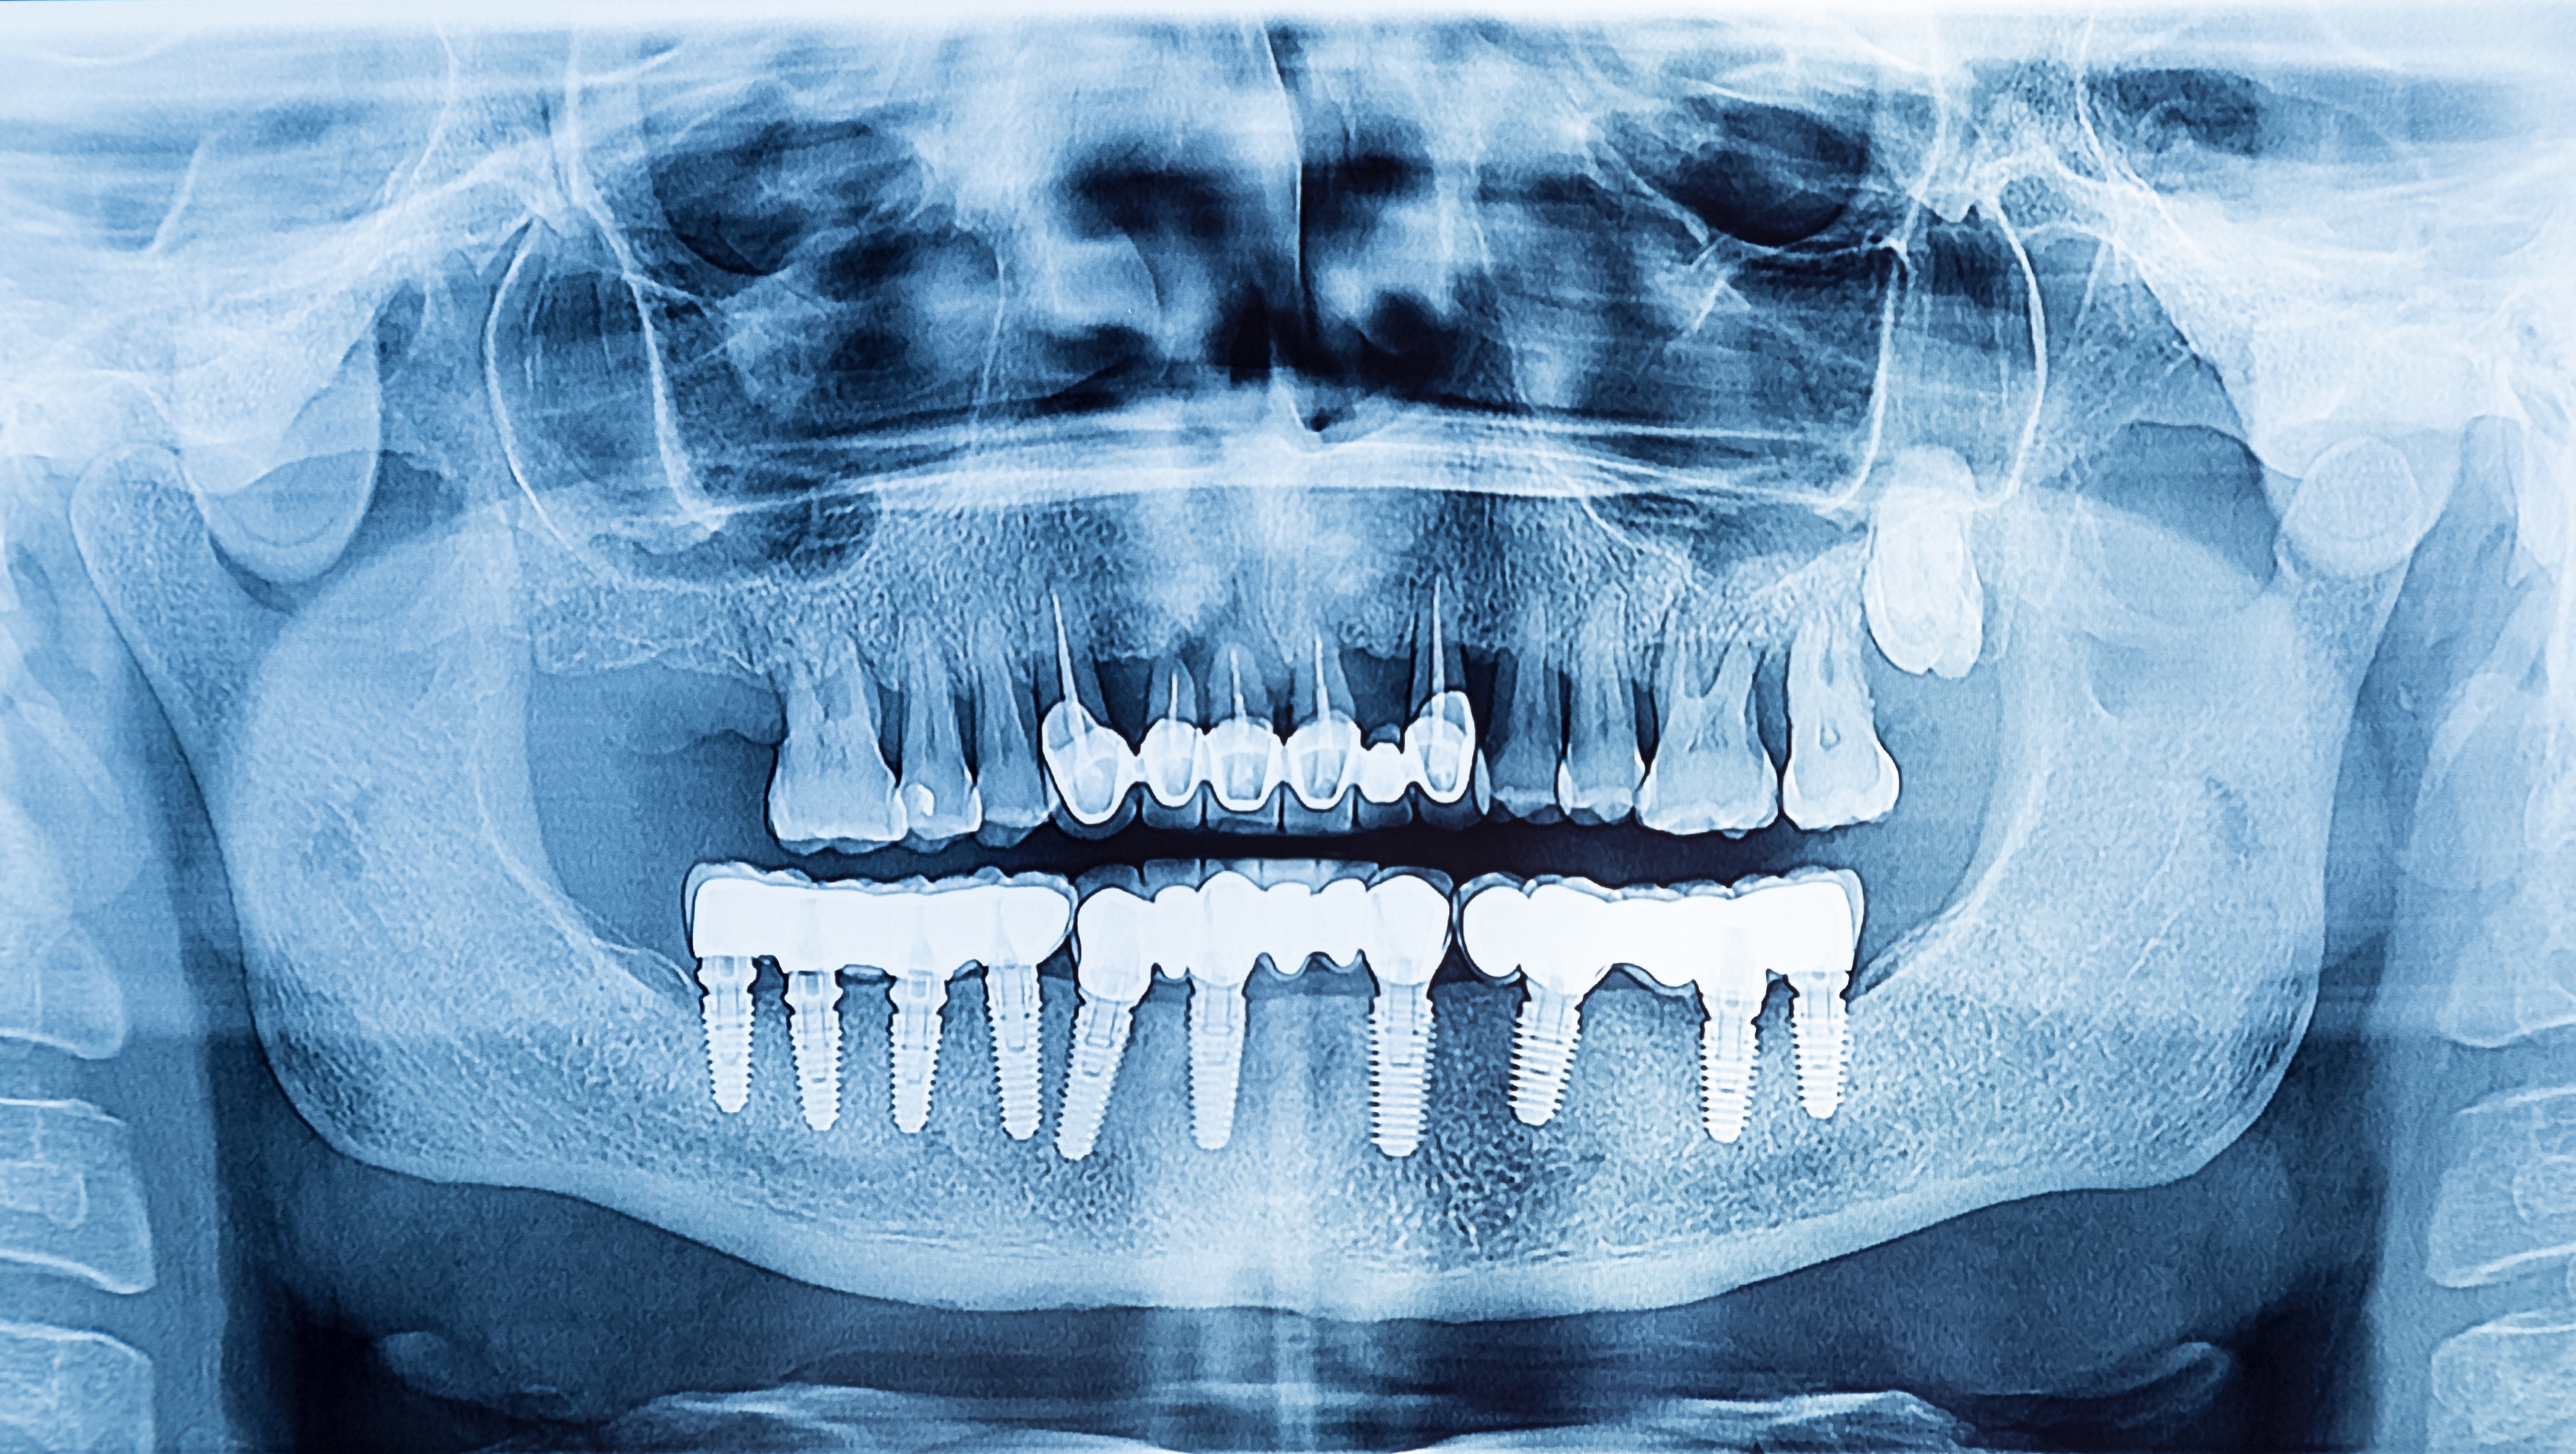

To be able to diagnose peri-implant diseases correctly, it is helpful to have good-quality, informative X-rays. However, periapical bitewing X-rays of implants in particular can often turn out blurry. There is, however, one very simple rule you can follow to correct these images and to depict implant threads clearly and precisely, thus enabling exact determination of the patient’s bone level. Furthermore, this rule is easy to remember and, above all, can be implemented rapidly in daily clinical practice: